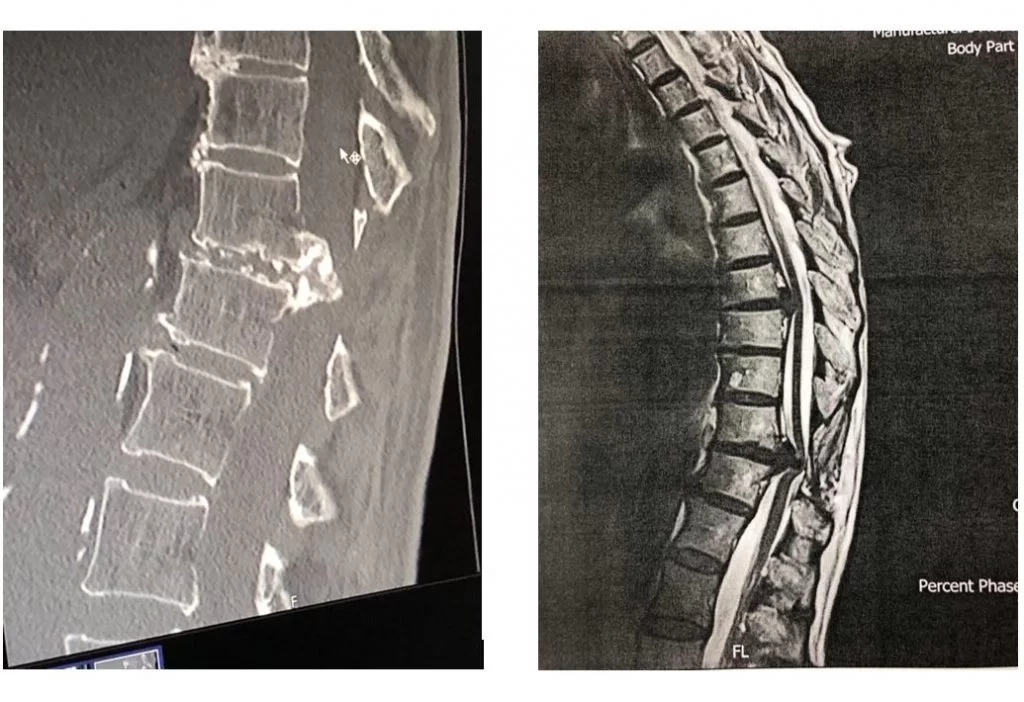

Με την πάροδο του χρόνου οι μεσοσπονδύλιοι δίσκοι μπορεί να υποστούν φθορά και να προβάλουν προς τα πίσω, πιέζοντας το νωτιαίο μυελό και τα νεύρα. Μάλιστα, συχνά, στη θωρακική μοίρα οι δισκοκήλες είναι επασβεστωμένες ή συνοδεύονται από μεγάλα οστεόφυτα (Εικόνα 1)